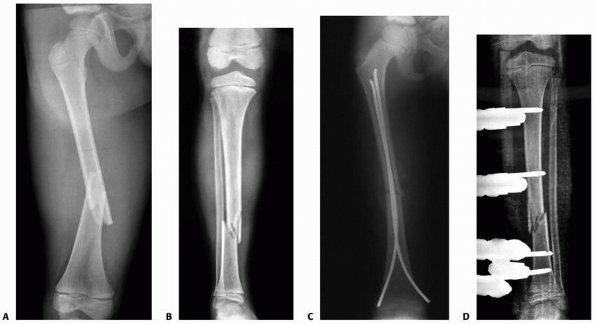

![]() |

|

FIGURE 25-28 A. Fracture of the distal tibia in a 7-year-old child. The lateral radiograph demonstrates a mild recurvatum deformity. B.

The ankle was initially immobilized in an ankle neutral position, producing an increased recurvatum deformity. The cast was removed and the ankle remanipulated into plantarflexion to reduce the deformity. C. The ankle was then immobilized in plantarflexion, which is the proper position for this type of fracture. |

FIGURE 25-29 A,B. Unstable distal metadiaphyseal fractures of the tibia and fibula in a 15-year-old girl. C. This fracture was stabilized with percutaneous pins because of marked swelling and fracture instability.

FIGURE 25-30 A.

Anteroposterior radiograph of a distal one-third tibial and fibular fractures in a 9-year-old girl with a closed head injury and severe spasticity. The initial reduction in a cast could not be maintained. B. Open reduction and internal fixation with a medial buttress plate was used to achieve and maintain the alignment. |